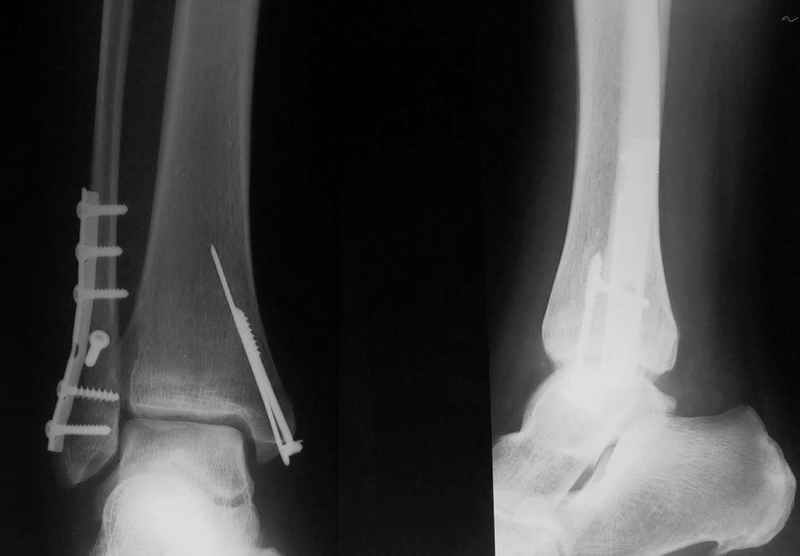

Стабильность г\ст сустава обеспечивается во-первых наружной лодыжкой (ключ), во-вторых задним краем б\б кости, в-третьих связками синдесмоза и межкостной мемраной, только в-четвертых медиальной лодыжкой (дельтовидной связкой. Это классика! А пяточной кости и плюсневых костей здесь нет! зачем их фиксировать? см. вложенный файл.